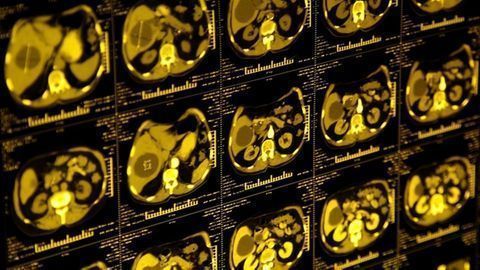

A low-dose CT for lung cancer screening can also predict a five-year cardiovascular disease risk of death when using a deep learning algorithm.